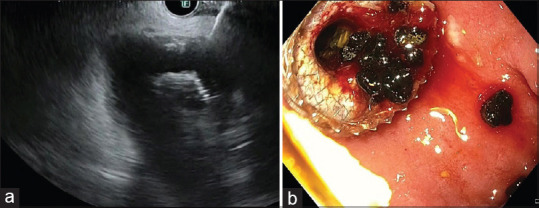

Abstract: Endoscopic ultrasonography (EUS) has progressed beyond diagnostic imaging to include EUS-guided tissue acquisition and EUS-directed therapies. This review provides an update on EUS-guided drainage and anastomotic procedures, and other therapeutic procedures. Today, EUS-guided drainage of symptomatic walled-off pancreatic fluid collections is the norm, with endoscopic necrosectomy as an adjunct. For high-risk surgical patients unsuitable for cholecystectomy, EUS-guided gallbladder drainage of acute cholecystitis is an option. Additionally, EUS-guided drainage of obstructed biliary and pancreatic ductal system can be performed as salvage procedures after unsuccessful endoscopic retrograde cholangiopancreatography (ERCP). Bariatric procedures such as Roux-en-Y gastric bypass alter the gastric anatomy, hindering access to the major papilla. This can be overcome by creating a conduit through the excluded stomach using EUS-directed transgastric ERCP. Gastric outlet obstruction and afferent loop syndrome can be treated using EUS-guided gastrojejunostomy. These therapeutic interventions are a major advancement in the field of interventional EUS, achieving significant clinical impact.